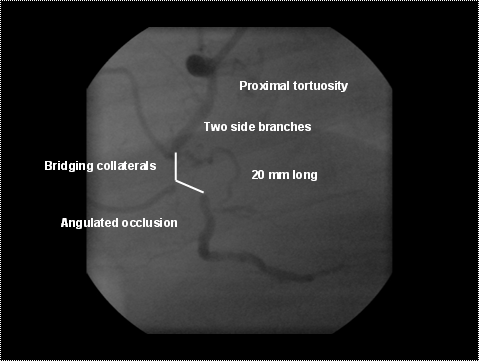

No intra-luminal antegrade flow (TIMI 0) beyond the point of occlusion. However, antegrade flow beyond the total occlusion might be maintained by bridging collaterals and/or ipsi collaterals.

At the question

‘Specify which segments are diseased for lesion X' one should only fill out the segment number of the start of the Total Occlusion.

Small channels running in parallel to the vessel and connecting proximal vessel to distal and being responsible for the ipsilateral collateralization.